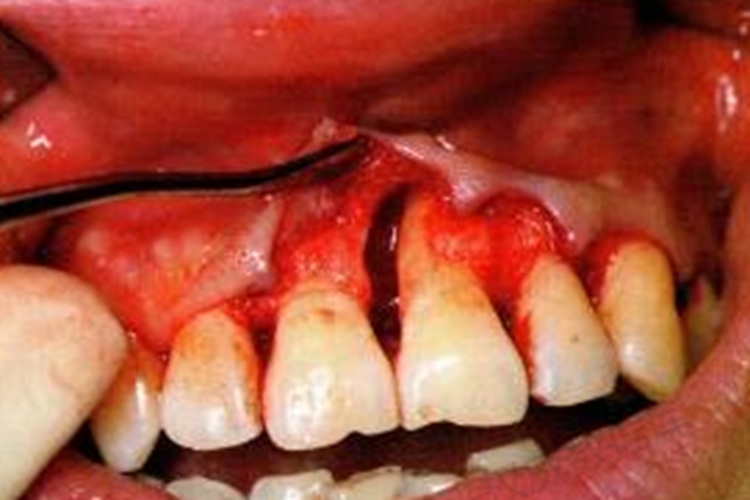

症状

牙槽骨吸收是牙周炎的另一个主要病理变化,通常会造成牙齿的支持组织丧失,出现牙齿逐渐松动,甚至导致牙齿脱落或拔除的情况。

牙槽骨吸收常通过X线片观察,主要显示牙齿近远中的骨质情况。牙周炎的骨吸收最初表现为牙槽嵴顶的硬骨学板消失,或嵴顶模糊呈虫蚀状。嵴顶的少量吸收使前牙的牙槽间隔由尖变平或凹陷,在后牙则使嵴顶由宽平变凹陷,以后牙槽骨高度降低。牙槽嵴顶到釉牙骨质界的距离超过2mm,可视为牙槽骨吸收。